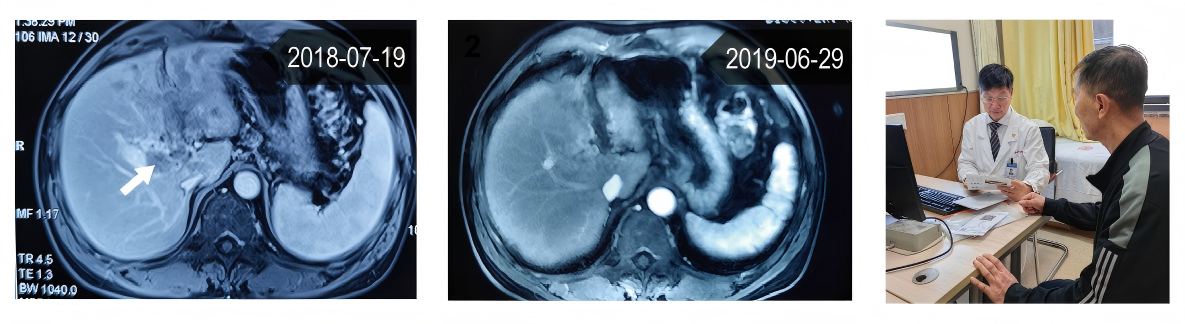

该患者在2018年7月就诊,接受3次TACE疗法,并联合TCC鸡尾酒疗法,已生存7年。图片均由研究团队提供